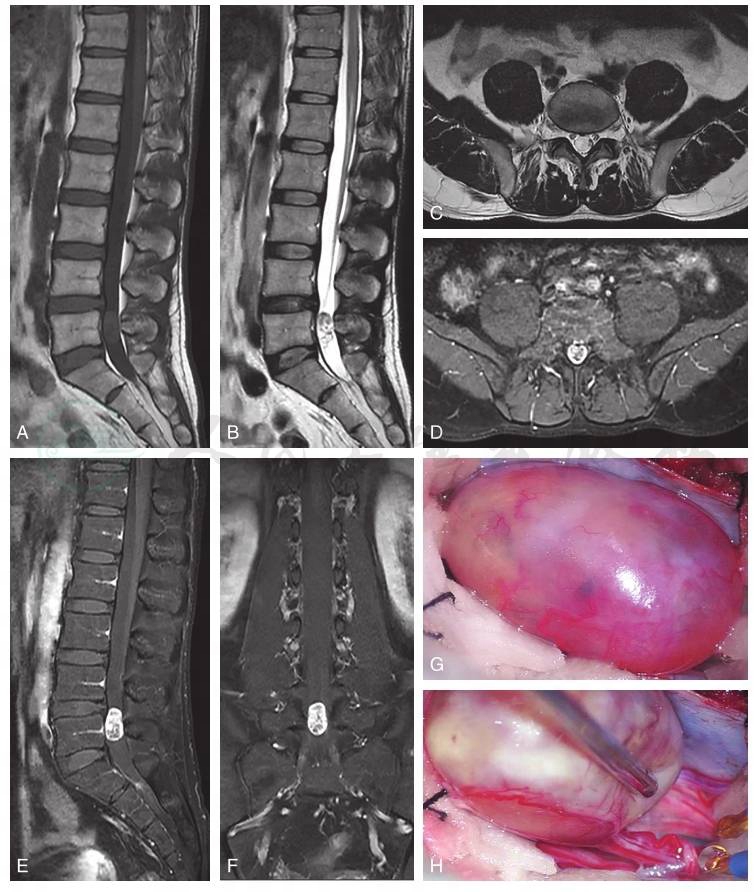

图5L5椎体水平实性成分为主的神经鞘瘤

腰椎MRI显示L5椎体水平占位性病变,T1(A)加权像矢状位呈稍高信号,T2加权像矢状位(B)和轴位(C)呈高信号为主的混杂信号,T1增强像轴位(D)、矢状位(E)和冠状位扫描(F)可见病变呈明显强化,内部可见小灶性非强化区。术中可见病变呈实性(G),载瘤神经根位于病变腹侧(H),邻近肿瘤部位神经根营养血管明显迂曲、扩张。

引自:周围神经外科学.第1版.ISBN:978-7-117-33415-0.主编: